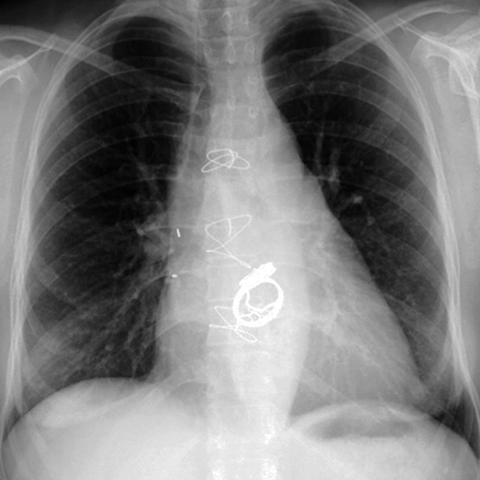

Prosthetic Aortic & Mitral Valves (PA CXR) [4 of 5]